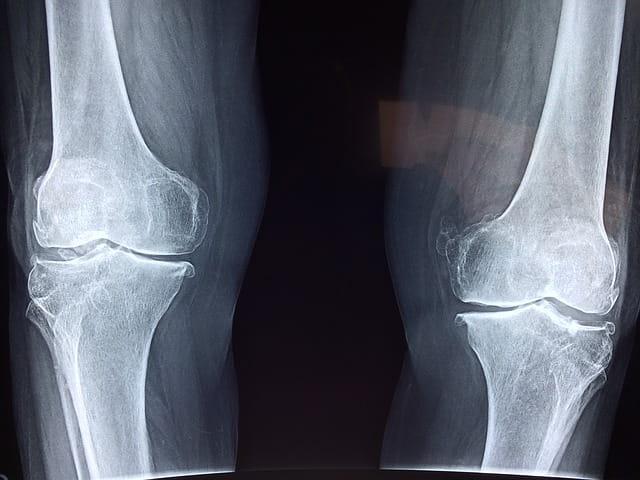

A osteoartrite é uma doença degenerativa que acomete a cartilagem das articulações sinoviais e osso subjacente. Mas esta doença pode aumentar a mortalidade? Confira:

A síndrome da dor patelofemoral é um distúrbio comum que afeta a articulação do joelho e acomete atletas como corredores, ciclistas, jogadores de tênis, etc.